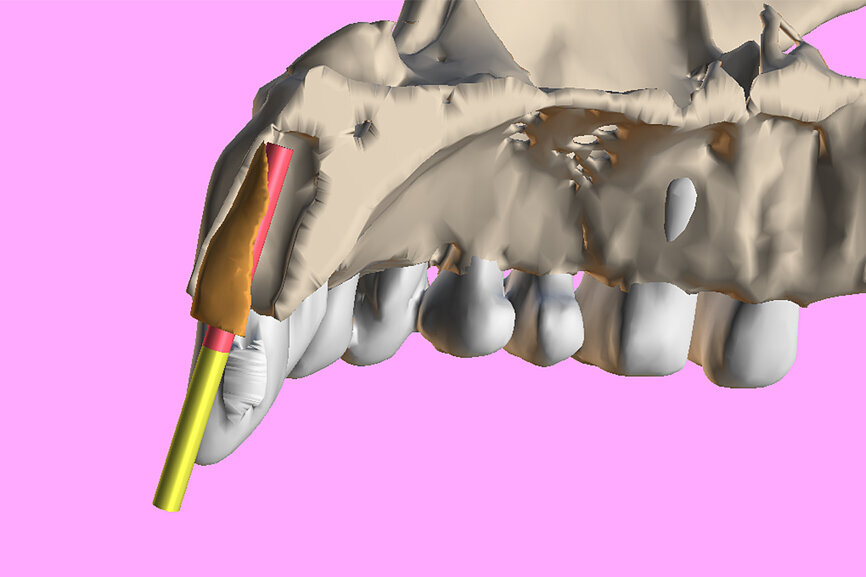

Fig. 3a: Planning the initial drill path using a custom implant design (red) to match the

diameter of the initial drill to reach the tooth apex. The abutment projection is shown in yellow.

3b: The simulated implant within the Triangle of Bone (red), placed to avoid the root fragment seen in yellow (white arrows).

One indication for PET is when a patient presents with a horizontally fractured clinical crown (Fig. 1). While a 2D radiograph will reveal the extent of the horizontal fracture, length of the remaining root and approximation of the bone apical to the root, there is not enough information to plan for a PET procedure. A CBCT scan is recommended in order to fully appreciate the root position within the alveolus and the potential difference between the trajectory of the bone and the trajectory of the root as can be visualised with a cross-sectional image (Fig. 2). Utilising interactive treatment planning software makes it possible to plan the initial drill path to accurately section the root to its apex (Fig. 3a). This can be accomplished by creating a custom implant design to match the diameter of the initial drill with an abutment projection in order to fully appreciate the trajectory through the clinical crown (Blue Sky Plan, Blue Sky Bio). It is important to visualise the root fragment that will remain in order to properly simulate the position of the implant in the alveolus (Fig. 3b). The apical portion of the implant can be positioned to gain stability in host bone using the Triangle of Bone. It is important to note that a cross-sectional slice may only be 0.125 mm in thickness based on the CBCT acquisition, and therefore all images in all views must be visualised to confirm the plan. Utilising 3D segmentation (separating objects by density values), it is possible to define each root and further assess the simulated position of the implant with a sagittal cut through the 3D reconstructed volume (Fig. 4).